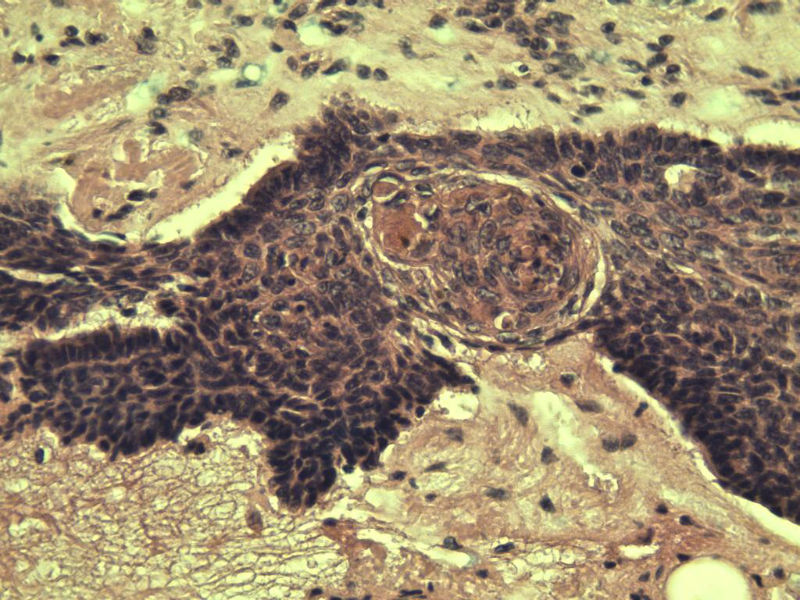

女 67岁 临床考虑面部色素痣 1*0.8 cm  请问各位老师 这是什么? 谢谢!面部包块图1

毛母/发细胞瘤鉴别基底细胞癌,可做CD10,CK7,CK20鉴别

考虑毛发上皮瘤,需除外基底细胞癌。

毛发上皮瘤,需与基底细胞癌鉴别

第一例:毛发上皮瘤

第一例:毛发上皮瘤,与基底细胞瘤区别明显。

第一例  毛发上皮瘤,和基底细胞癌鉴别一下

第一例考虑毛母细胞瘤,第二例考虑基底细胞癌。

毛母细胞瘤

第一例:毛母细胞瘤;第二例:基底细胞癌

第一例,毛发上皮瘤;第二例,基底细胞癌。

一毛发上皮瘤